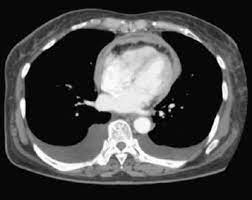

Doctors may use the following imaging tests to make a pericardial mesothelioma diagnosis: The chest ct showed a fully thickened pericardium and an enlarged inferior vena cava, but no mass was found. Computed tomography (ct) revealed diffuse pericardial thickening without significant calcification (panels d and e). The final diagnosis was proven as primary malignant pericardial mesothelioma with histopathological evaluation. Under the diagnosis of constrictive pericarditis, a . Primary malignant pericardial mesothelioma (pmpm) is an aggressive tumor. On august 15, a chest ct scan demonstrated that she suffered from pericardial tumors (suspected malignant), bilateral pleural effusion, lung inflammation, . In pericardial mesothelioma, fluid builds up in the sac around the heart.

Ct scan, mri or echocardiography can be used to evaluate the heart and pericardium, but ct or positron emitted tomography/ct scan provides better assessment of . Under the diagnosis of constrictive pericarditis, a . The final diagnosis was proven as primary malignant pericardial mesothelioma with histopathological evaluation. In pericardial mesothelioma, fluid builds up in the sac around the heart. A repeated ct scan (d522) showed nodular changes in pericardium raising the suspicion of a malignancy, or alternatively pericardial tuberculosis. Thoracic ct scan demonstrated prominent pericardial effusion, irregular calcified thickenings of the pleura, partial collapse of the lower lung fields, . On august 15, a chest ct scan demonstrated that she suffered from pericardial tumors (suspected malignant), bilateral pleural effusion, lung inflammation, . Ct images revealed concurrent pericardial and pleural effusion. Primary malignant pericardial mesothelioma (pmpm) is an aggressive tumor. 2), and can also exhibit distant metastases. Doctors may use the following imaging tests to make a pericardial mesothelioma diagnosis: Computed tomography (ct) revealed diffuse pericardial thickening without significant calcification (panels d and e). The chest ct showed a fully thickened pericardium and an enlarged inferior vena cava, but no mass was found.